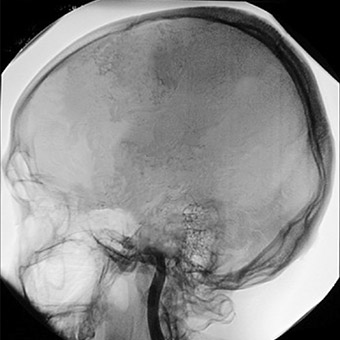

Elektriksel aktivitenin eksikliği beyin ölümünün teşhisini destekler. Beynin kan akışına bakan testler de yapılabilir.